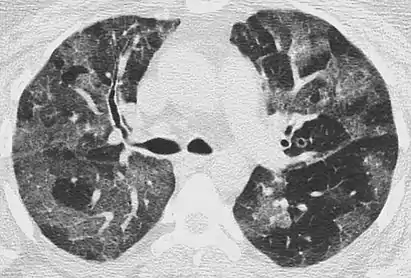

Mosaic

A mosaic pattern of GGO refers to multiple irregular areas of both increased attenuation and decreased attenuation on CT. It is often the result of occlusion of small pulmonary arteries or obstruction of small airways leading to air trapping.[6] Sarcoidosis is an additional cause of a mosaic GGOs due to the formation of granulomas in interstitial areas. This may coexist with granulomatosis with polyangiitis, leading to diffuse areas of increased attenuation with ground-glass appearance.[6]